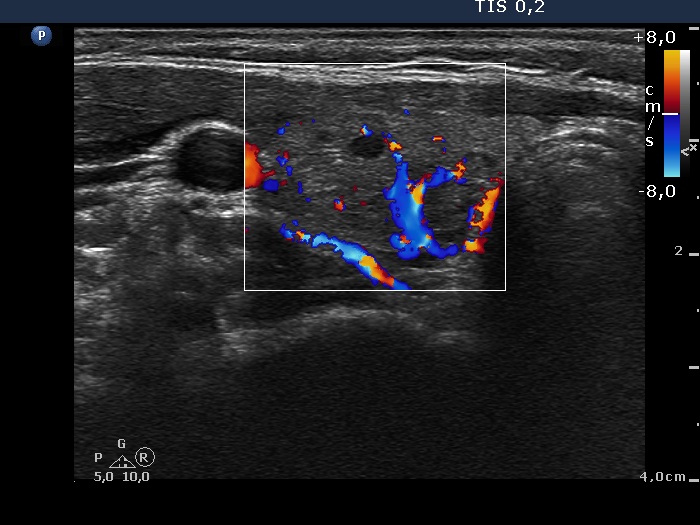

Ultrasonography. The thyroid was echonormal. There were multiple moderately hypoechogenic lesions in the right lobe. The palpable nodule was echonormal and presented halo sign and perinodular blood flow.